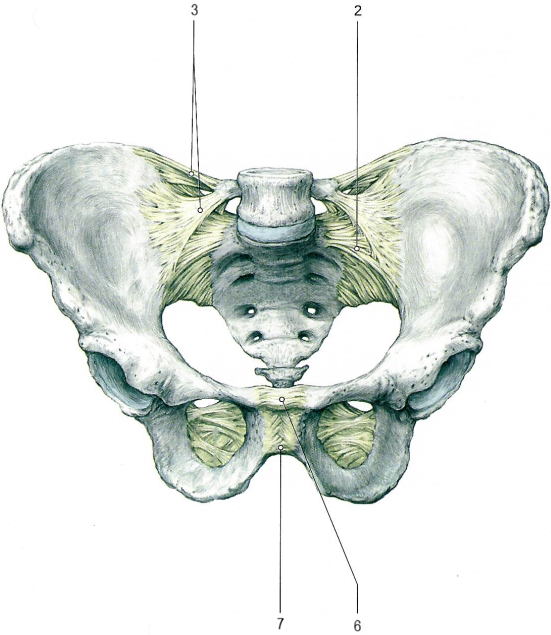

Крестцово-позвздошный сустав по строению простой, по форме плоский, по функции многоосный, однако движения в суставе отвутствуют.

Сустав образован ушковидными поверхностями подвздошной кости и крестца.

Связки, укрепляющие сустав.

Лобковый симфиз[II] соединяет симфизиальные поверхности двух лобковых костей, между которыми расположен волокнисто-хрящевой межлобковый диск.

Лобковый симфиз укреплён следующими связками:

Лобковый симфиз имеет ярко выраженные половые особенности. У женщин это соединение менее высокое и более толстое. Во время родов у женщин в лобковом симфизе возможны небольшие движения.

Помимо суставов и укрепляющих их связок, тазовые кости соединяются с крестцом с помощью двух мощных внекапсульных связок.